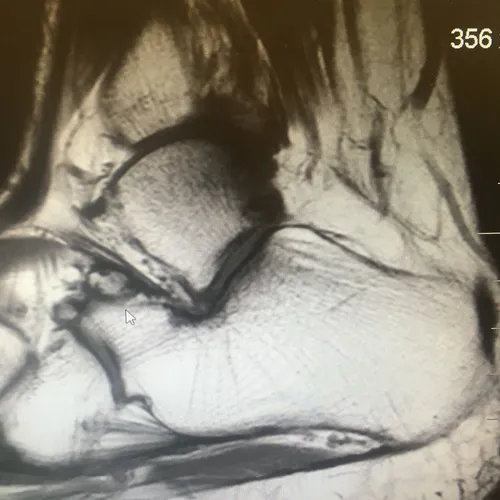

Below, MRI of a nonunion of an anterior process avulsion fracture (Shown above th white arrow)